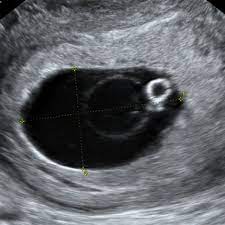

Embarazo de localización desconocida es un término usado para describir la situación en la que la paciente tiene una prueba de embarazo positiva, pero se desconoce la localización y viabilidad del embarazo porque no se encuentra en la ecografía.